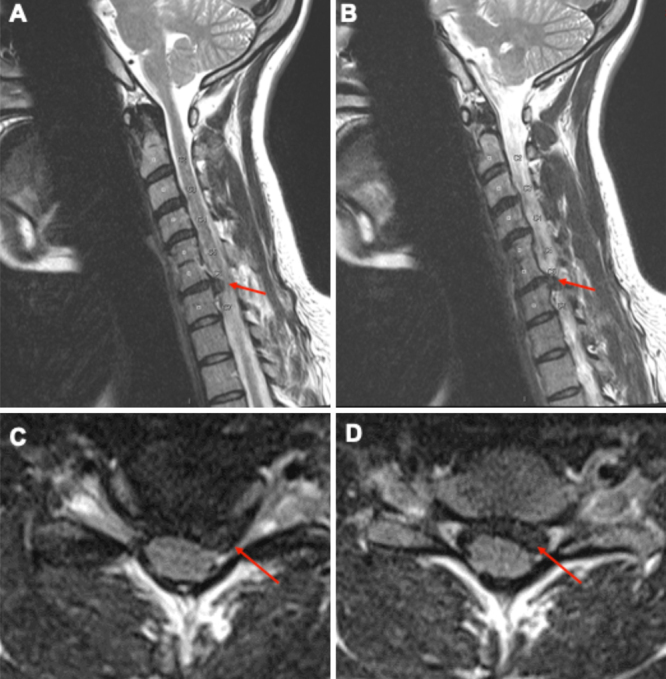

Observations: The authors present the case of a woman in her mid-30s at 24 weeks of gestation, conceived via in vitro fertilization, who developed progressively worsening left C7 radiculopathy refractory to conservative therapies. After comprehensive multidisciplinary evaluation, she underwent successful anterior cervical discectomy and fusion with placement of a stand-alone interbody cage. Perioperative planning incorporated anesthetic modifications, fetal monitoring strategies, and minimization of radiation exposure. The patient experienced immediate postoperative relief, rapid functional recovery, and an uncomplicated pregnancy course.